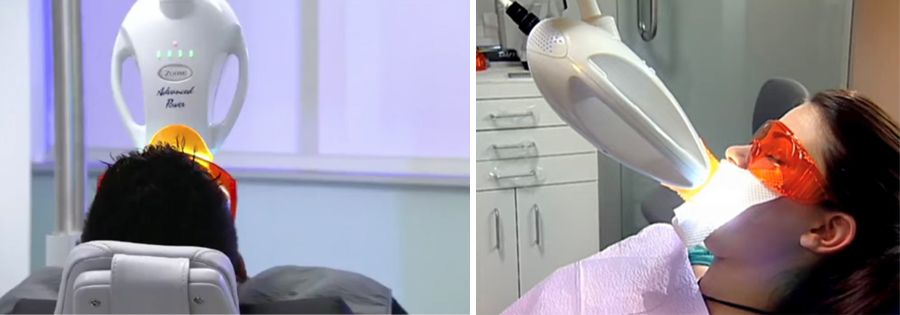

מכשיר הלבנת השיניים החדשני של חברת PHILIPS – מכשיר ההלבנה המתקדם ביותר בעולם בעידן החדש של הלבנות שיניים אשר מתבצעות במרפאות.

המכשיר מצויד במנורת LED חדשנית אשר עובדת עם אור קר, ובניגוד למכשירים מוכרים, אשר עד היום עובדים על אור חם, האור הקר מונע העברת חום לשיניים ושומר עליהן בפני כל נזק, מעלה את יעילות ונוחות הטיפול תוך השגת תוצאות הלבנה מקסימליות תוך 45 דקות בלבד.

תהליך הלבנת שיניים בשיטת ZOOM הינו פשוט מאד, נטול כאב או אי נוחות ונותן תוצאות מיידיות, עד 8 דרגות שינוי בגוון.

בשיטה זו, קרני ה- UV גורמות לאקטיבציה של חומר ההלבנה ובכך משפרות את תוצאות הטיפול באופן משמעותי כאשר זמן הטיפול מתקצר.